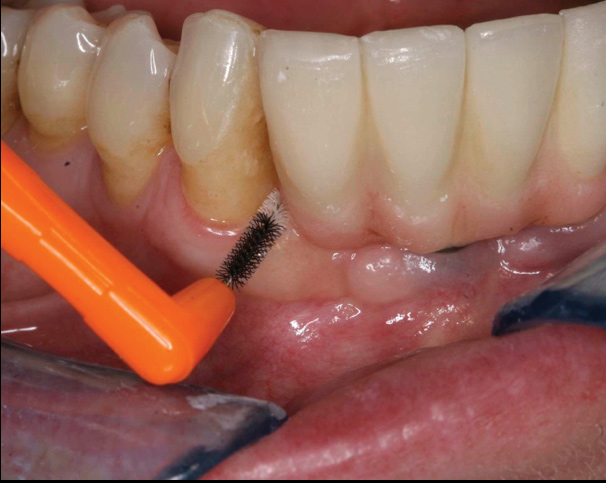

The first step in preventive strategies must be to perform a correct diagnosis of the peri-implant condition by accurately assessing the health of the peri-implant hard and soft tissues through periodontal probing and periapical radiographs at the time of definitive prosthetic installation. These measurements should be considered the baseline diagnosis and, therefore, represent a true starting point for evaluating the changes on the radiographic bone levels and probing pocket depths (PPD) at future recall appointments (Figure 1 and Figure 2).6 Although probing depth measurements of peri-implant tissues do not have the same diagnostic value as probing periodontal tissues, there is evidence that BOP is the most objective sign of peri-implant tissue inflammation; significant deepening of PPD compared with baseline measurements is also a sign of disease that indicates the need to perform a radiographic evaluation (Figure 3 through Figure 5).6,10,11

Fig 1. Baseline measurements at the time of prosthetic delivery: probing pocket depth and

Figure 1

Fig 2. periapical radiographs.

Figure 2